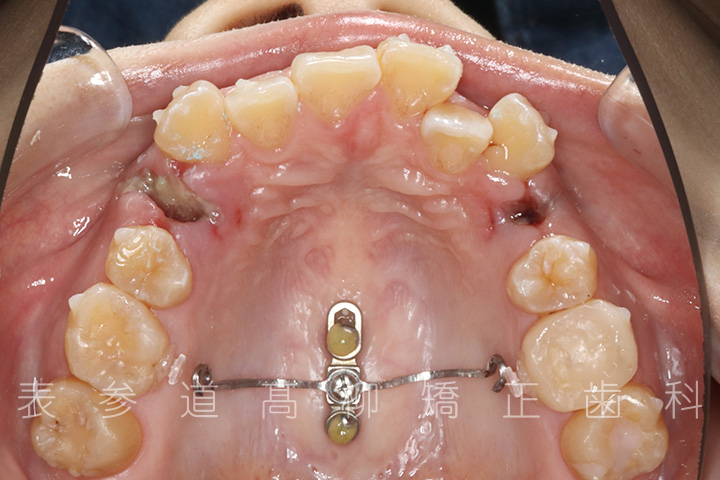

前歯のガタガタ感と開咬でお悩みの患者様の症例をご紹介いたします。

・前歯部開咬

・上下前歯部叢生(凸凹歯並び)

・上顎左右第一小臼歯、下顎左右第二小臼歯を抜歯の抜歯

・マウスピース型矯正装置と歯科矯正用アンカースクリュー(i-station)を併用し、上顎臼歯部を圧下

・歯科矯正用アンカースクリュー(i-station)を併用し、前歯部を後方へ移動する

・歯科矯正用アンカースクリューを併用し、口下顎大臼歯の近心移動(前方への移動)

・上下歯列の緊密な咬合関係の確立に顎間ゴムを併用(装着時間20時間以上/日)

術前術後の比較